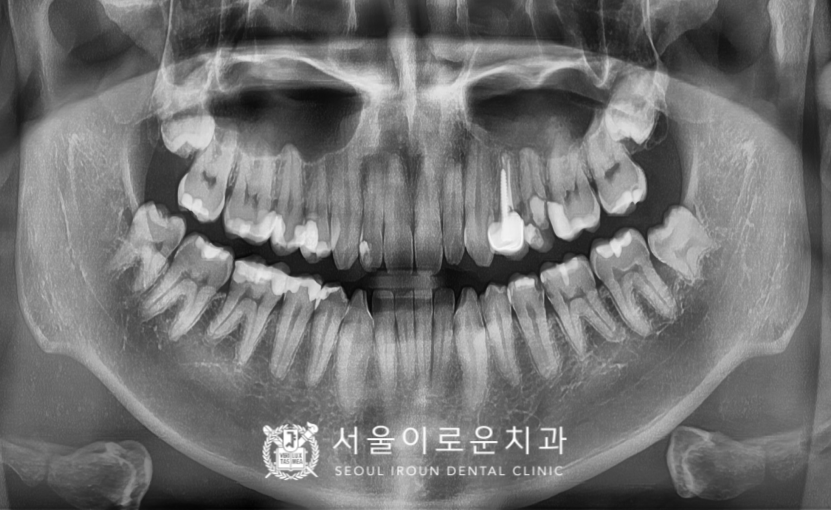

부천시청역치과 서울이로운치과에서

모든 치.료가 마무리된 후 촬영한

파노라마 사진입니다.

임플란트 / 신경치료 / 크라운치료 /

인레이치료 / 발치를

모두 잘 도와드렸답니다.